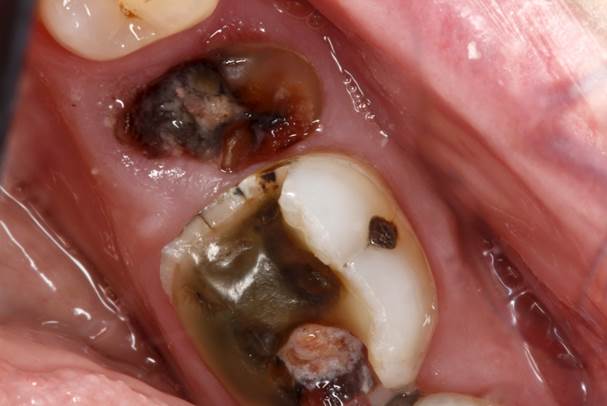

An abscessed tooth is a painful condition in which a pocket of pus forms around the tooth. The tooth abscess can be caused by bacteria that enter the tooth through a crack or chip, or it can occur after an injury to the tooth. Treatment for an abscessed tooth usually involves antibiotics and drainage of the abscess. In some cases, the tooth may need to be removed.

A tooth abscess is a pus-filled sac that forms at the end of a tooth’s root. The main cause of a tooth abscess is an infection, which can be the result of bacteria, a cracked tooth, a cavity, or gum disease. A cracked tooth allows bacteria to enter the pulp, or innermost layer, of the tooth. Once inside the pulp, the bacteria begin to multiply and spread through the root canal system. Gum disease occurs when plaque buildup causes inflammation and infection in the gums. This can lead to an abscessed tooth if the infection spreads to the bone supporting the teeth.